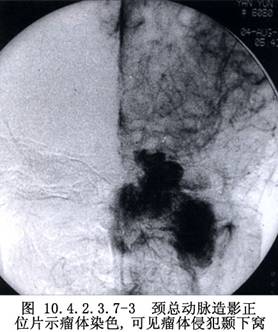

3.供血丰富的良性肿瘤,如巨型血管瘤,神经纤维瘤,颈动脉体瘤,鼻咽纤维血管瘤,颈静脉球体瘤等(图10.4.2.3.7-3,10.4.2.3.7-4)。